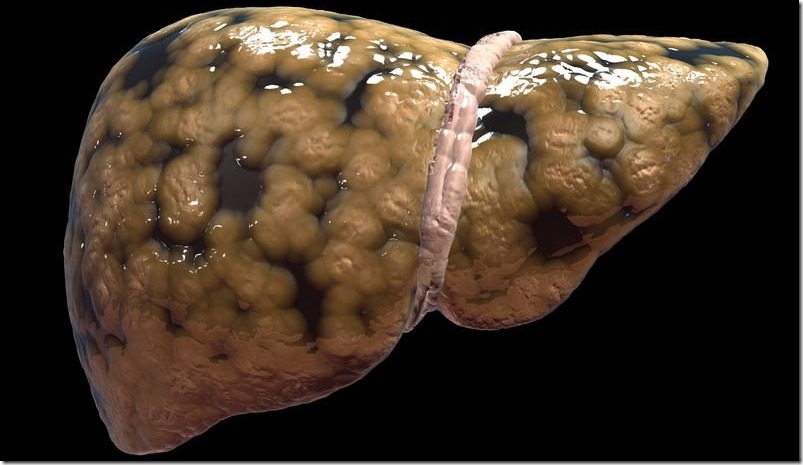

A pesar de que el hígado es el encargado de limpiar nuestro cuerpo, llega un momento en que tenemos que limpiar el hígado para que funcione correctamente. El consumo excesivo de alimentos procesados, ingesta de alcohol, productos químicos, la contaminación, entre otros, puede hacer que nuestro hígado se sobrecargue en sus tareas y deje de funcionar correctamente. Como consecuencia a la acumulación de toxinas en el hígado, se pueden derivar otros problemas de salud que pueden afectar otros sistemas de nuestro cuerpo.

El hígado es el órgano interno más grande y la glándula más grande del cuerpo humano. El hígado juega un papel vital en muchas funciones corporales que van desde la producción de proteínas a través de la coagulación de la sangre y también regula los niveles de colesterol, glucosa y el metabolismo de hierro. Y filtrando continuamente nuestra sangre, el hígado desintoxica y limpia nuestros cuerpos. A excepción del cerebro el hígado es el órgano más complejo, por lo que mantenerlo en buen estado de salud es imperativo. Un punto único y muy positivo es que nuestro hígado es realmente capaz de repararse a sí mismo, lo que significa que, dependiendo de la causa del daño y si es detectada a tiempo, pueden de hecho hacer recuperaciones completas.

La manera principal de eliminar las toxinas del cuerpo es a través del hígado, que desintoxica y limpia el cuerpo de forma continua filtrando de la sangre los venenos que entran a través del tracto digestivo, la piel y el sistema respiratorio. Pero cuando el hígado tiene un exceso de trabajo como resultado del estrés o la exposición excesiva a las toxinas, todo el sistema puede perder el equilibrio, y tu salud puede verse seriamente comprometida.

Dado que el hígado es también responsable de la producción de bilis, otra forma de desintoxicación que es metabólicamente necesaria para la descomposición y asimilación de las grasas y las proteínas de los alimentos, es sumamente importante que tu hígado se mantenga de forma adecuada. Sin un hígado que funcione bien, tu cuerpo será incapaz de limpiarse por sí mismo y absorber los nutrientes, lo que es una forma segura para perder la salud.